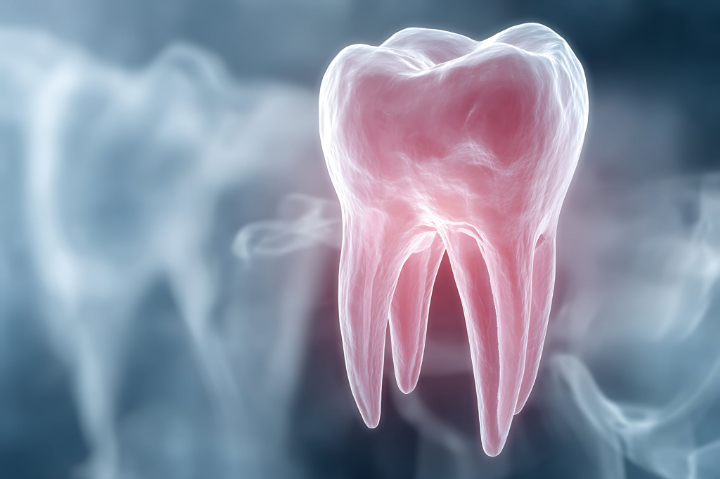

親知らずとは、正式には第三大臼歯(だいさんだいきゅうし)と呼ばれる歯で、上下左右の最も奥に位置する永久歯です。通常、左右の上下4本が存在しますが、なかには4本すべてがそろわない人もいます。